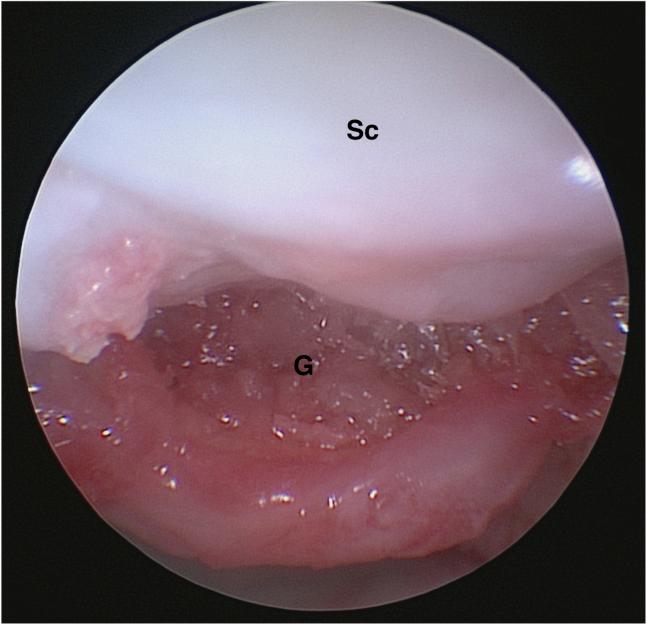

Intraosseous lunate bone ganglia (ILBG) are known to be a cause of chronic wrist pain and disability. Standard treatment consists of curettage and autologous bone grafting. Open procedures have shown good results with few recurrences, but with frequent stiffness or persistent pain. Arthroscopic techniques are more recent and seem very reliable. Several arthroscopic techniques have been reported for ILBG approach and treatment. The present study describes an approach that preserves all the lunate cartilage of both radiocarpal and midcarpal surfaces. The surgical technique allows easy and direct access to the bone ganglia, passing through the intermediate portion of the scapholunate ligament, with the scope in the 1-to-2 portal and instrumentation through the 3-to-4 portal. The rest of the procedure is straightforward: curettage and bone grafting are performed through this specific approach, similarly to other techniques. This an easy and accurate approach that avoids any damage to the major cartilage surfaces of the lunate, with easy and reliable access to the intraosseous lunate bone ganglion, allowing cyst curettage and autologous bone graft in a proper and noninvasive way.

骨内月骨囊肿(ILBG)是慢性腕部疼痛和功能障碍的一个已知病因。标准治疗方法包括刮除术和自体骨移植。开放性手术已显示出良好的效果,复发率低,但常伴有僵硬或持续性疼痛。关节镜技术是较新的方法,似乎非常可靠。已有多种关节镜技术用于ILBG的入路和治疗。本研究描述了一种保留桡腕关节和腕中关节月骨所有软骨面的入路方法。该手术技术通过舟月韧带的中间部分,将关节镜置于1-2通道,器械通过3-4通道,从而能够轻松、直接地进入骨囊肿。其余步骤很简单:与其他技术类似,通过这种特定入路进行刮除术和骨移植。这是一种简单而精确的入路方法,可避免对月骨主要软骨面造成任何损伤,能够轻松、可靠地进入月骨内骨囊肿,以适当且无创的方式进行囊肿刮除和自体骨移植。